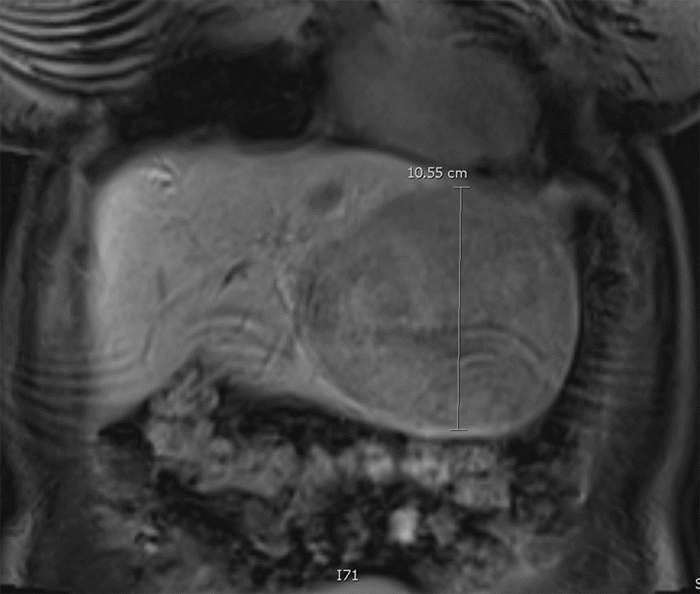

Figure 1. Preoperative Liver MRI. Published with Permission

(A) Axial coronal gadoxetate-enhanced MRI liver image demonstrating a 10.6 × 12.1 × 6.8 cm left lobe segment II-IV lesion exhibiting heterogeneous enhancement that persists into the hepatobiliary phase, along with a T2-hypointense central scar. Additionally, two areas consistent with focal nodular hyperplasia are identified in segments IVb and VI, along with three small (~1 cm) lesions likely consistent with hepatic adenomas in segments VI and VII

(B) coronal gadoxetate-enhanced MRI liver image demonstrating a 10.6 × 12.1 × 6.8 cm left lobe segment II-IV lesion exhibiting heterogeneous enhancement that persists into the hepatobiliary phase, along with a T2-hypointense central scar. Additionally, two areas consistent with focal nodular hyperplasia are identified in segments IVb and VI, along with three small (~1 cm) lesions likely consistent with hepatic adenomas in segments VI and VII.